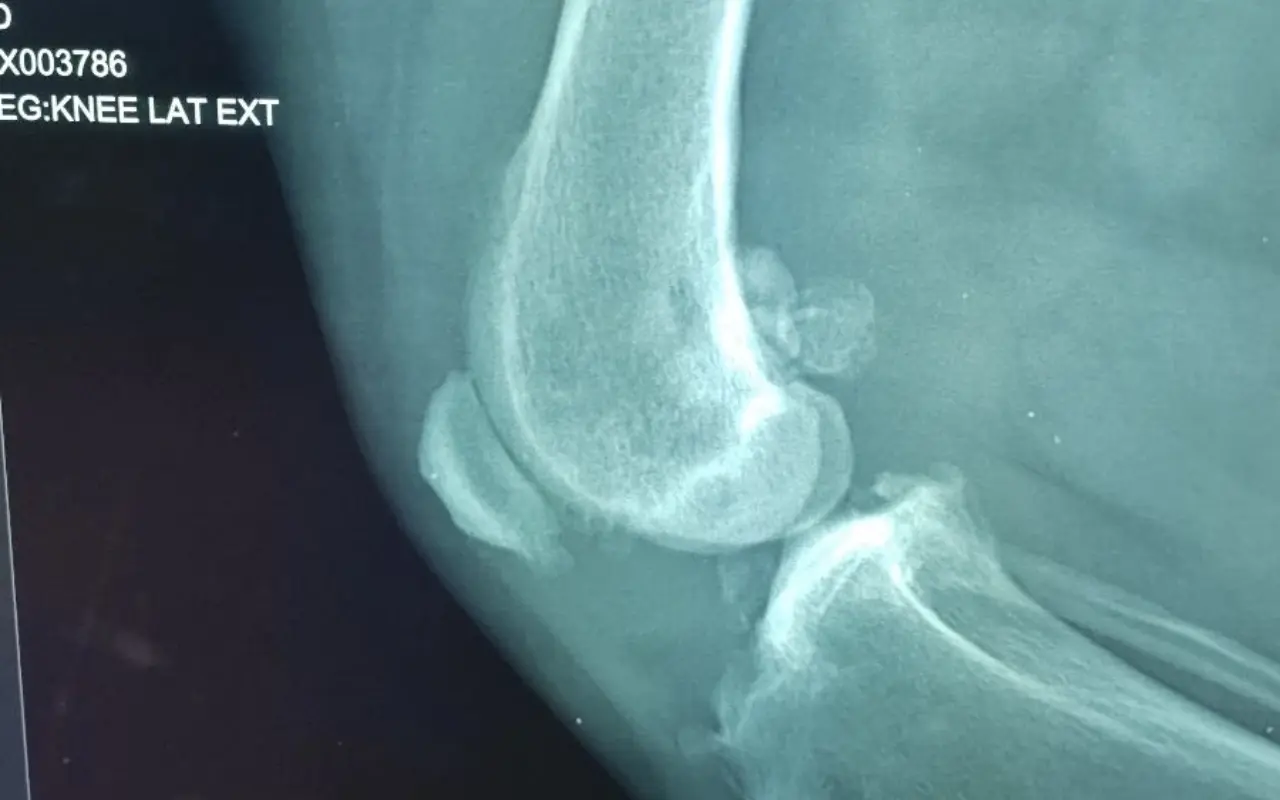

Korenovy nález na páteří, Schromovy uzly, plotenky, velmi rizikové jít na operaci z důvodu polymorbidni a meyabolickeho syndromu, vše není operovatelne, berle a vice metrů než 30 s podporou osoby